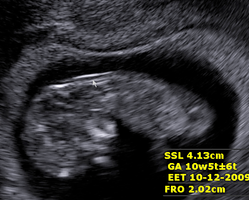

Frühestzeitige Diagnosemöglichkeit- auch und besonders mit Ultraschall.

1. Ersttrimesteruntesuchung mit Ultraschall

3. Untersuchung ab 10. SSW